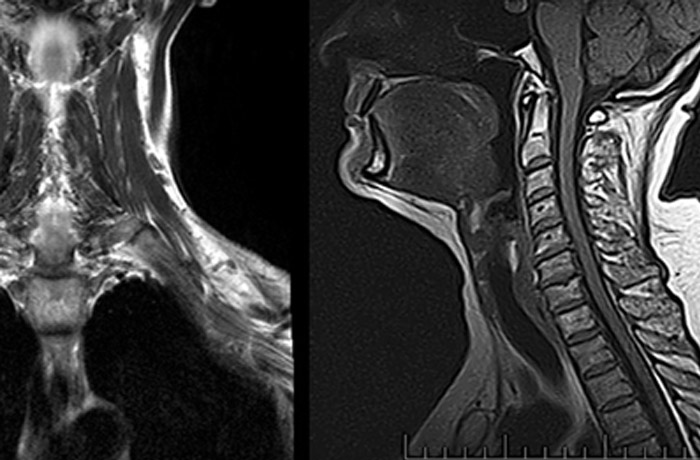

МРТ шейного отдела позвоночника направлено на выявление различных повреждений позвоночника, спинного мозга и патологии дисков. Исследование позволяет диагностировать следующие заболевания:

МР-диагностика шейного отдела позвоночника